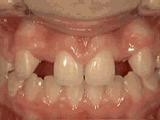

第五种:

前牙开合,即使闭嘴,上下牙齿也不接触,留出空隙,经过矫正后的牙齿是这样的~